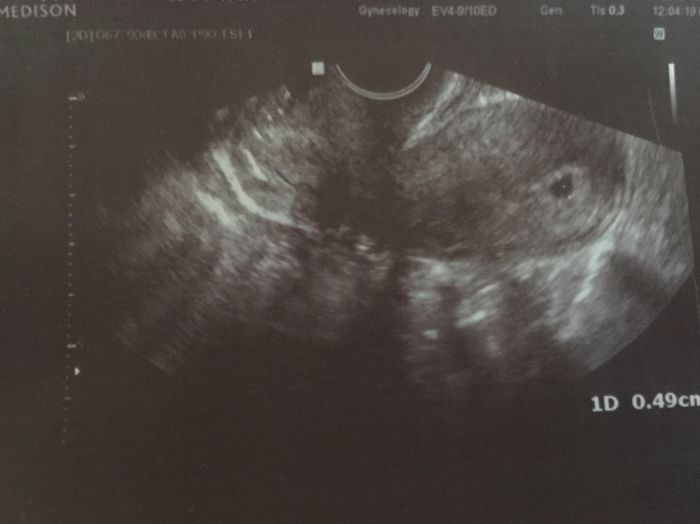

Ta mala tečka vpravo...no, tak šestý týden asi...ale doktor ti řekne